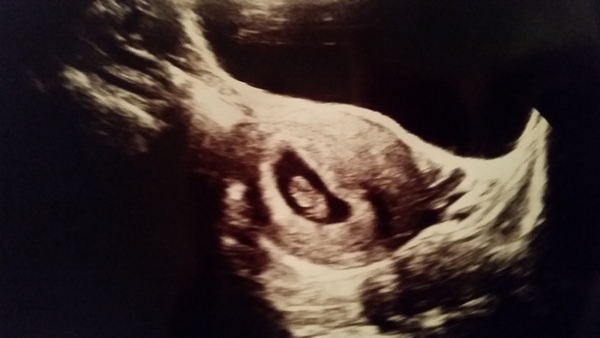

Soda that's a beautiful little scan!

Wow! That's an amazing scan soda! Beautiful.

Glad the scan went well Soda.. Lovely pic

I passed out at our booking in appointment today which was really embarrassing. My blood pressure was low and she got into the 5th vial...well I just flaked at that point! Anyway all is ok because we saw baby miley today!

Oh soda how amazing! I can't believe how much changes in 4 weeks.

So pleased all scans went well and that babies are all progressing nicely - there are some brilliant pictures! I'm assuming there is only one baby in there Miley?! I know you were worried about the possibility of twins. How are you feeling now?

pink yes only one bean! Was the first thing I asked. I was like definitely? You're definitely sure? There's no way it can be hiding? I feel really good, sickness isn't as harsh tonight luckily so I'm having some milky way cheesecake

A bumper crop of lovely scans - hooray! Danni is it your turn tomorrow?

That's a wonderful picture Soda

Lovely scan Miley!

Lovely scan miley, must favs been lovely after the tough time you've been having. I had an early scan too and yes, completely amazing how much it grows in a few weeks!

Only just seen your scan Miley lovely scan of your Bean X

Here's my little plum...